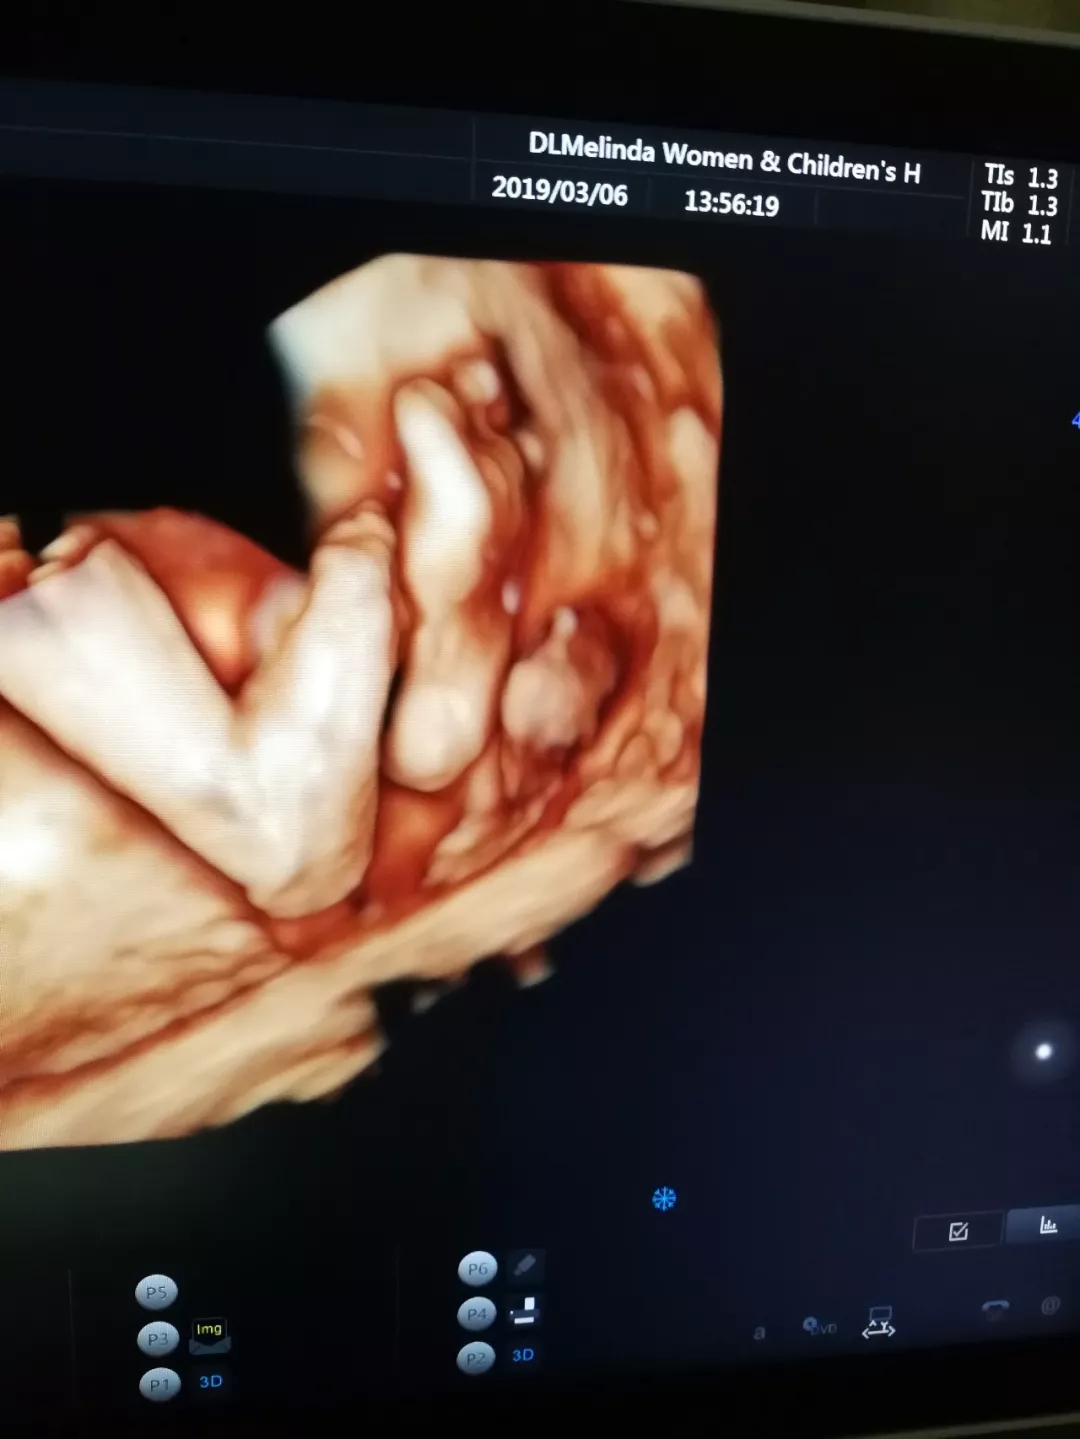

“妈妈,告诉您哦~我“十八般武艺”样样都精通

当您感觉到胎动的时候,有可能是我刚睡醒,在伸伸胳膊、扭扭身子、蹬蹬腿,但我的绝招是,我能在您的肚子里练拳,练侧踢,没事还能来个前空翻、后空翻呢。我最喜爱的玩具是我的脐带,我可以抓着它绕圈圈,可是有时候玩着玩着,脐带就会缠在我的脖子上,但是妈妈您不用担心,我会一点点把脐带绕回去哒~”

但通过美琳达的四维彩超画面中

TA们的活泼好动,萌萌的表情

已经说明了一切